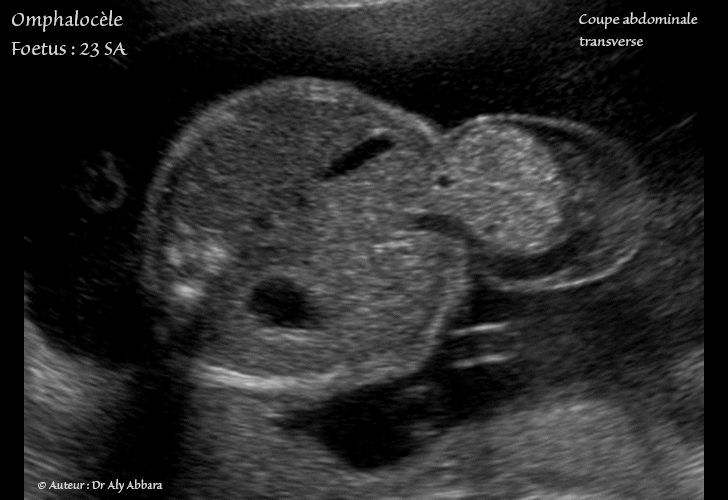

Omphalocèle isolée chez un foetus de 23 SA - Contenu composé des intestins exclusivement

Omphalocèle - Grossesse de 23 SA

• Images échographiques montrant une grossesse de 23 SA caractérisée par la présence d'une omphalocèle contenant seulement une partie des anses grêles ; la non fermeture de la paroi abdominale antérieure mesure 15 x 22 mm et elle se situe au niveau de l'ombilic (étage moyen de l'abdomen).

Le cordon ombilical s'insère sur le sac membraneux (le sac herniaire) entourant cette formation, puis il parcours son coté gauche avant d'entrer dans la cavité abdominale.

Aucune anomalie fœtales associée à cette omphalocèle.

Le caryotype fœtal ne montre pas d'anomalie chromosomique associée (46, XX).